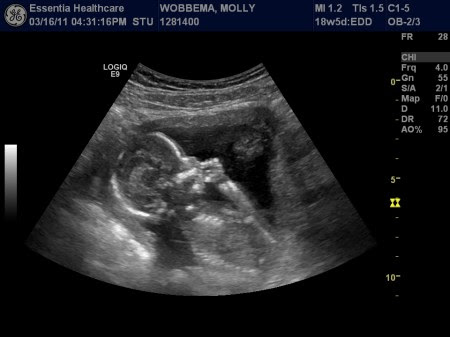

Today is August 8th. Just in case you stopped counting, that is 21 days, or 3 weeks from my due date (August 29). That is exciting news! However, based on the dates we told our doctor about when the pregnancy test became positive and all that jazz, our original due date was August 12. (He changed it after our 20 week ultrasound, saying that baby was measuring about 17 weeks.) But just in case you weren’t doing the math, August 12 just so happens to be this Friday. SO… I guess baby could come “early”. That’d be kind of fun!